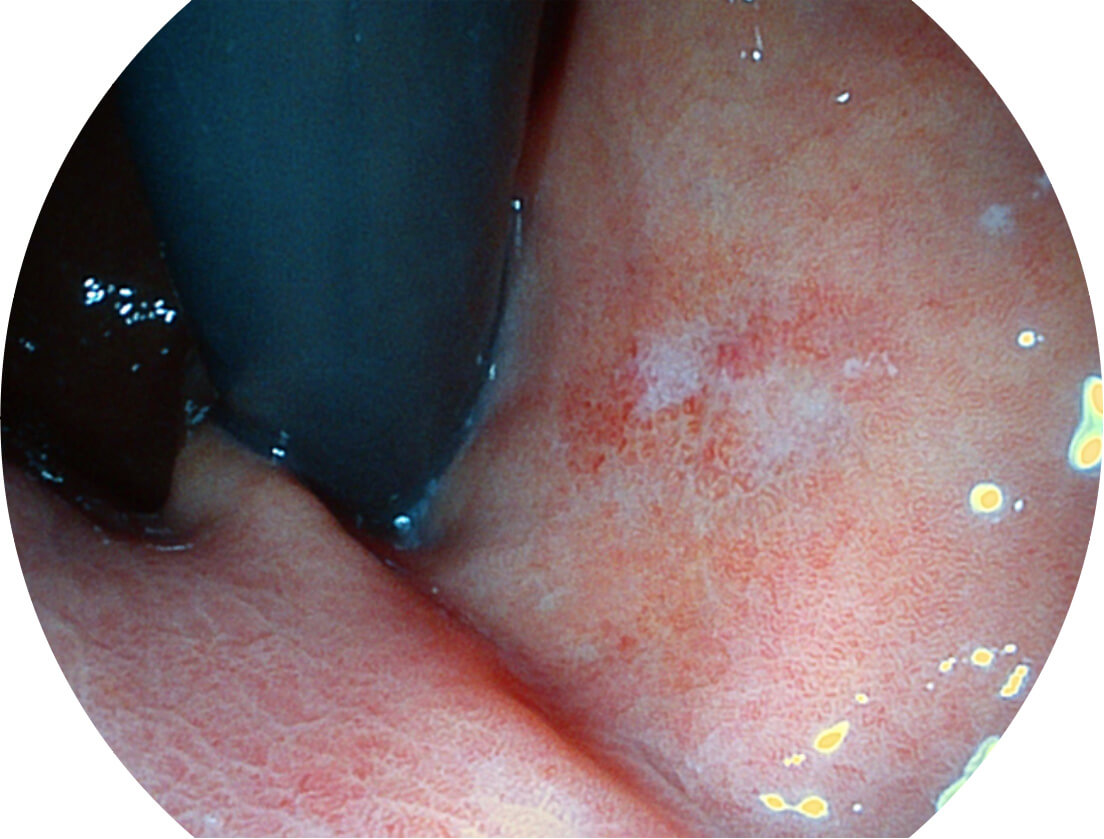

强调浅层黏膜结构的同时,保证照明亮度和提升浅层微血管与中层血管颜色对比度,病变边界更清晰。

VIST图像

送水方向与手术器械方向,两者更贴合,能快速冲洗黏膜表面的粘液及出血,发现病变和出血点。